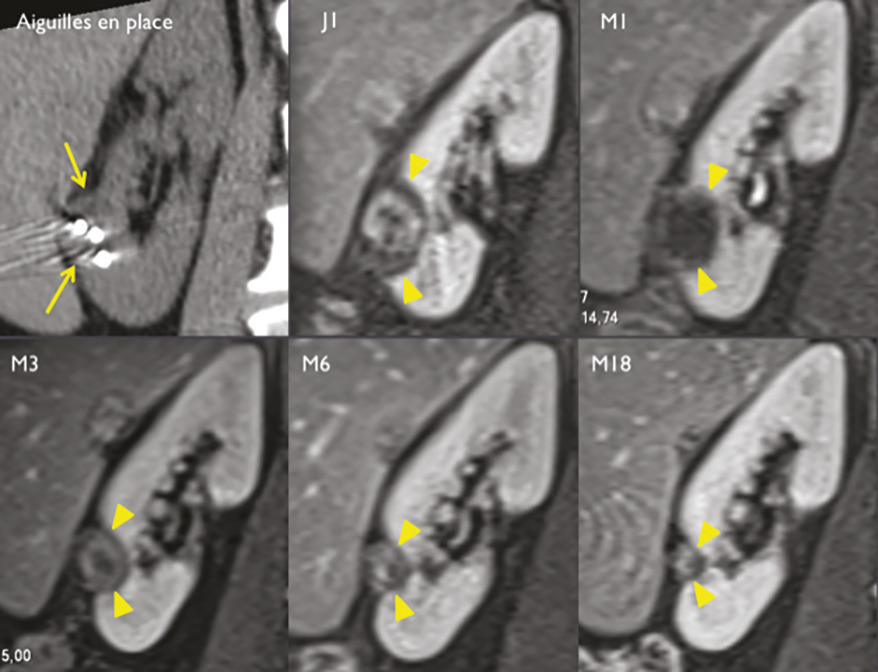

Pour chaque patient, un bilan d’hémostase est systématiquement réalisé avant la procédure. Pour les patients prenant des anticoagulants oraux, un relais par héparine de bas poids moléculaire est réalisé. Pour les antiagrégants plaquettaires, seul le clopidogrel doit être interrompu 5 jours avant. Le patient reçoit une prémédication par 1 g de paracétamol intraveineux 30 minutes avant la procédure. Il reste hospitalisé une nuit, mais une prise en charge ambulatoire est possible.La cryothérapie est réalisée sous anesthésie locale à l’aide d’un mélange de lidocaïne et de ropivacaïne. Contrairement à la radiofréquence ou aux micro-ondes où une seule électrode est insérée, la cryothérapie nécessite de mettre en place plusieurs aiguilles (cryoprobes) espacées au maximum de 15 mm afin de couvrir la totalité de la tumeur (fig. 1 ). Plus la tumeur est grosse, plus le nombre d’aiguilles à introduire est important. Il existe des abaques permettant de déterminer le nombre d’aiguilles optimal en fonction de la taille de la tumeur. Néanmoins, l’indication principale étant des tumeurs de stade T1a (< 4 cm de diamètre), le nombre moyen d’aiguilles est de 3, avec des extrêmes entre 2 et 5. Une injection de CO2 (carbodissection) ou de sérum physiologique (hydrodissection) est parfois nécessaire entre le rein et les organes adjacents afin de les éloigner de la zone d’ablation et les protéger.Les aiguilles sont mises en place sous tomodensitométrie et on vérifie leur bon positionnement. La dose délivrée lors d’une cryoablation rénale est inférieure aux niveaux de référence de dose recommandés pour une tomodensitométrie abdominale. Le traitement consiste en deux phases de cryoablation de 10 minutes entrecoupées d’une phase de réchauffement passif de 10 minutes également. L’effet cryogénique est obtenu par expansion d’un gaz (l’argon) dans une chambre de décompression de 2 à 4 cm de long située à l’extrémité de l’aiguille. Les températures minimales obtenues au contact de l’aiguille sont proches de -100 °C, en sachant qu’en moyenne la température de la tumeur se situe à -40 °C. La tomodensitométrie permet une excellente visualisation de la boule de glace, ce qui permet de monitorer l’ablation tout au long de la procédure. La boule de glace ainsi créée doit englober en totalité la tumeur et la dépasser de 5 mm afin d’avoir des marges de sécurité (fig. 2 ).6 En effet, le bord de la boule de glace est à l’isotherme 0 °C, qui n’est pas létal pour les tissus.Après traitement, le suivi des patients s’effectue par tomodensitométrie ou par imagerie par résonance magnétique (IRM), typiquement à 1 mois, 3 mois, 6 mois et 1 an, puis tous les ans. La zone d’ablation se rétracte progressivement et se fibrose, sans tumeur résiduelle visible (fig. 3 ). Pour les tumeurs de moins de 2 cm, le zone d’ablation disparaît parfois en totalité, laissant juste une encoche à la surface du rein (fig. 4 ). Les effets secondaires sont rares, la cryoablation étant mieux tolérée que les techniques d’ablation fondées sur le chauffage des lésions, en particulier pour les lésions proches de la voie excrétrice.7